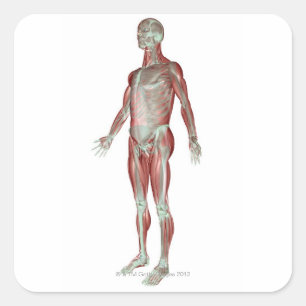

Impressão Em Tela Anatomia do corpo humano

PreçoR$ 572,00